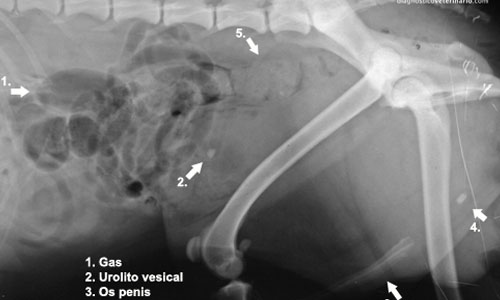

¿Cuál es tu diagnóstico?